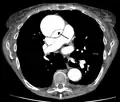

Computed tomography angiography is a fast, non-invasive test that gives an accurate three-dimensional view of the aorta. These images are produced by taking rapid, thin-cut slices of the chest and abdomen, and combining them in the computer to create cross-sectional slices. To delineate the aorta to the accuracy necessary to make the proper diagnosis, an iodinated contrast material is injected into a peripheral vein. Contrast is injected and the scan performed using a bolus tracking method. This type of scan is timed to injection to capture the contrast as it enters the aorta. The scan then follows the contrast as it flows through the vessel. It has a sensitivity of 96 to 100% and a specificity of 96 to 100%. Disadvantages include the need for iodinated contrast material and the inability to diagnose the site of the intimal tear.

- CT with contrast demonstrating aneurysmal dilation and a dissection of the ascending aorta (type A Stanford)

- Chest CT with descending (type B Stanford) aortic dissection (red circle)

- Type A dissection with pericardial effusion as a result.